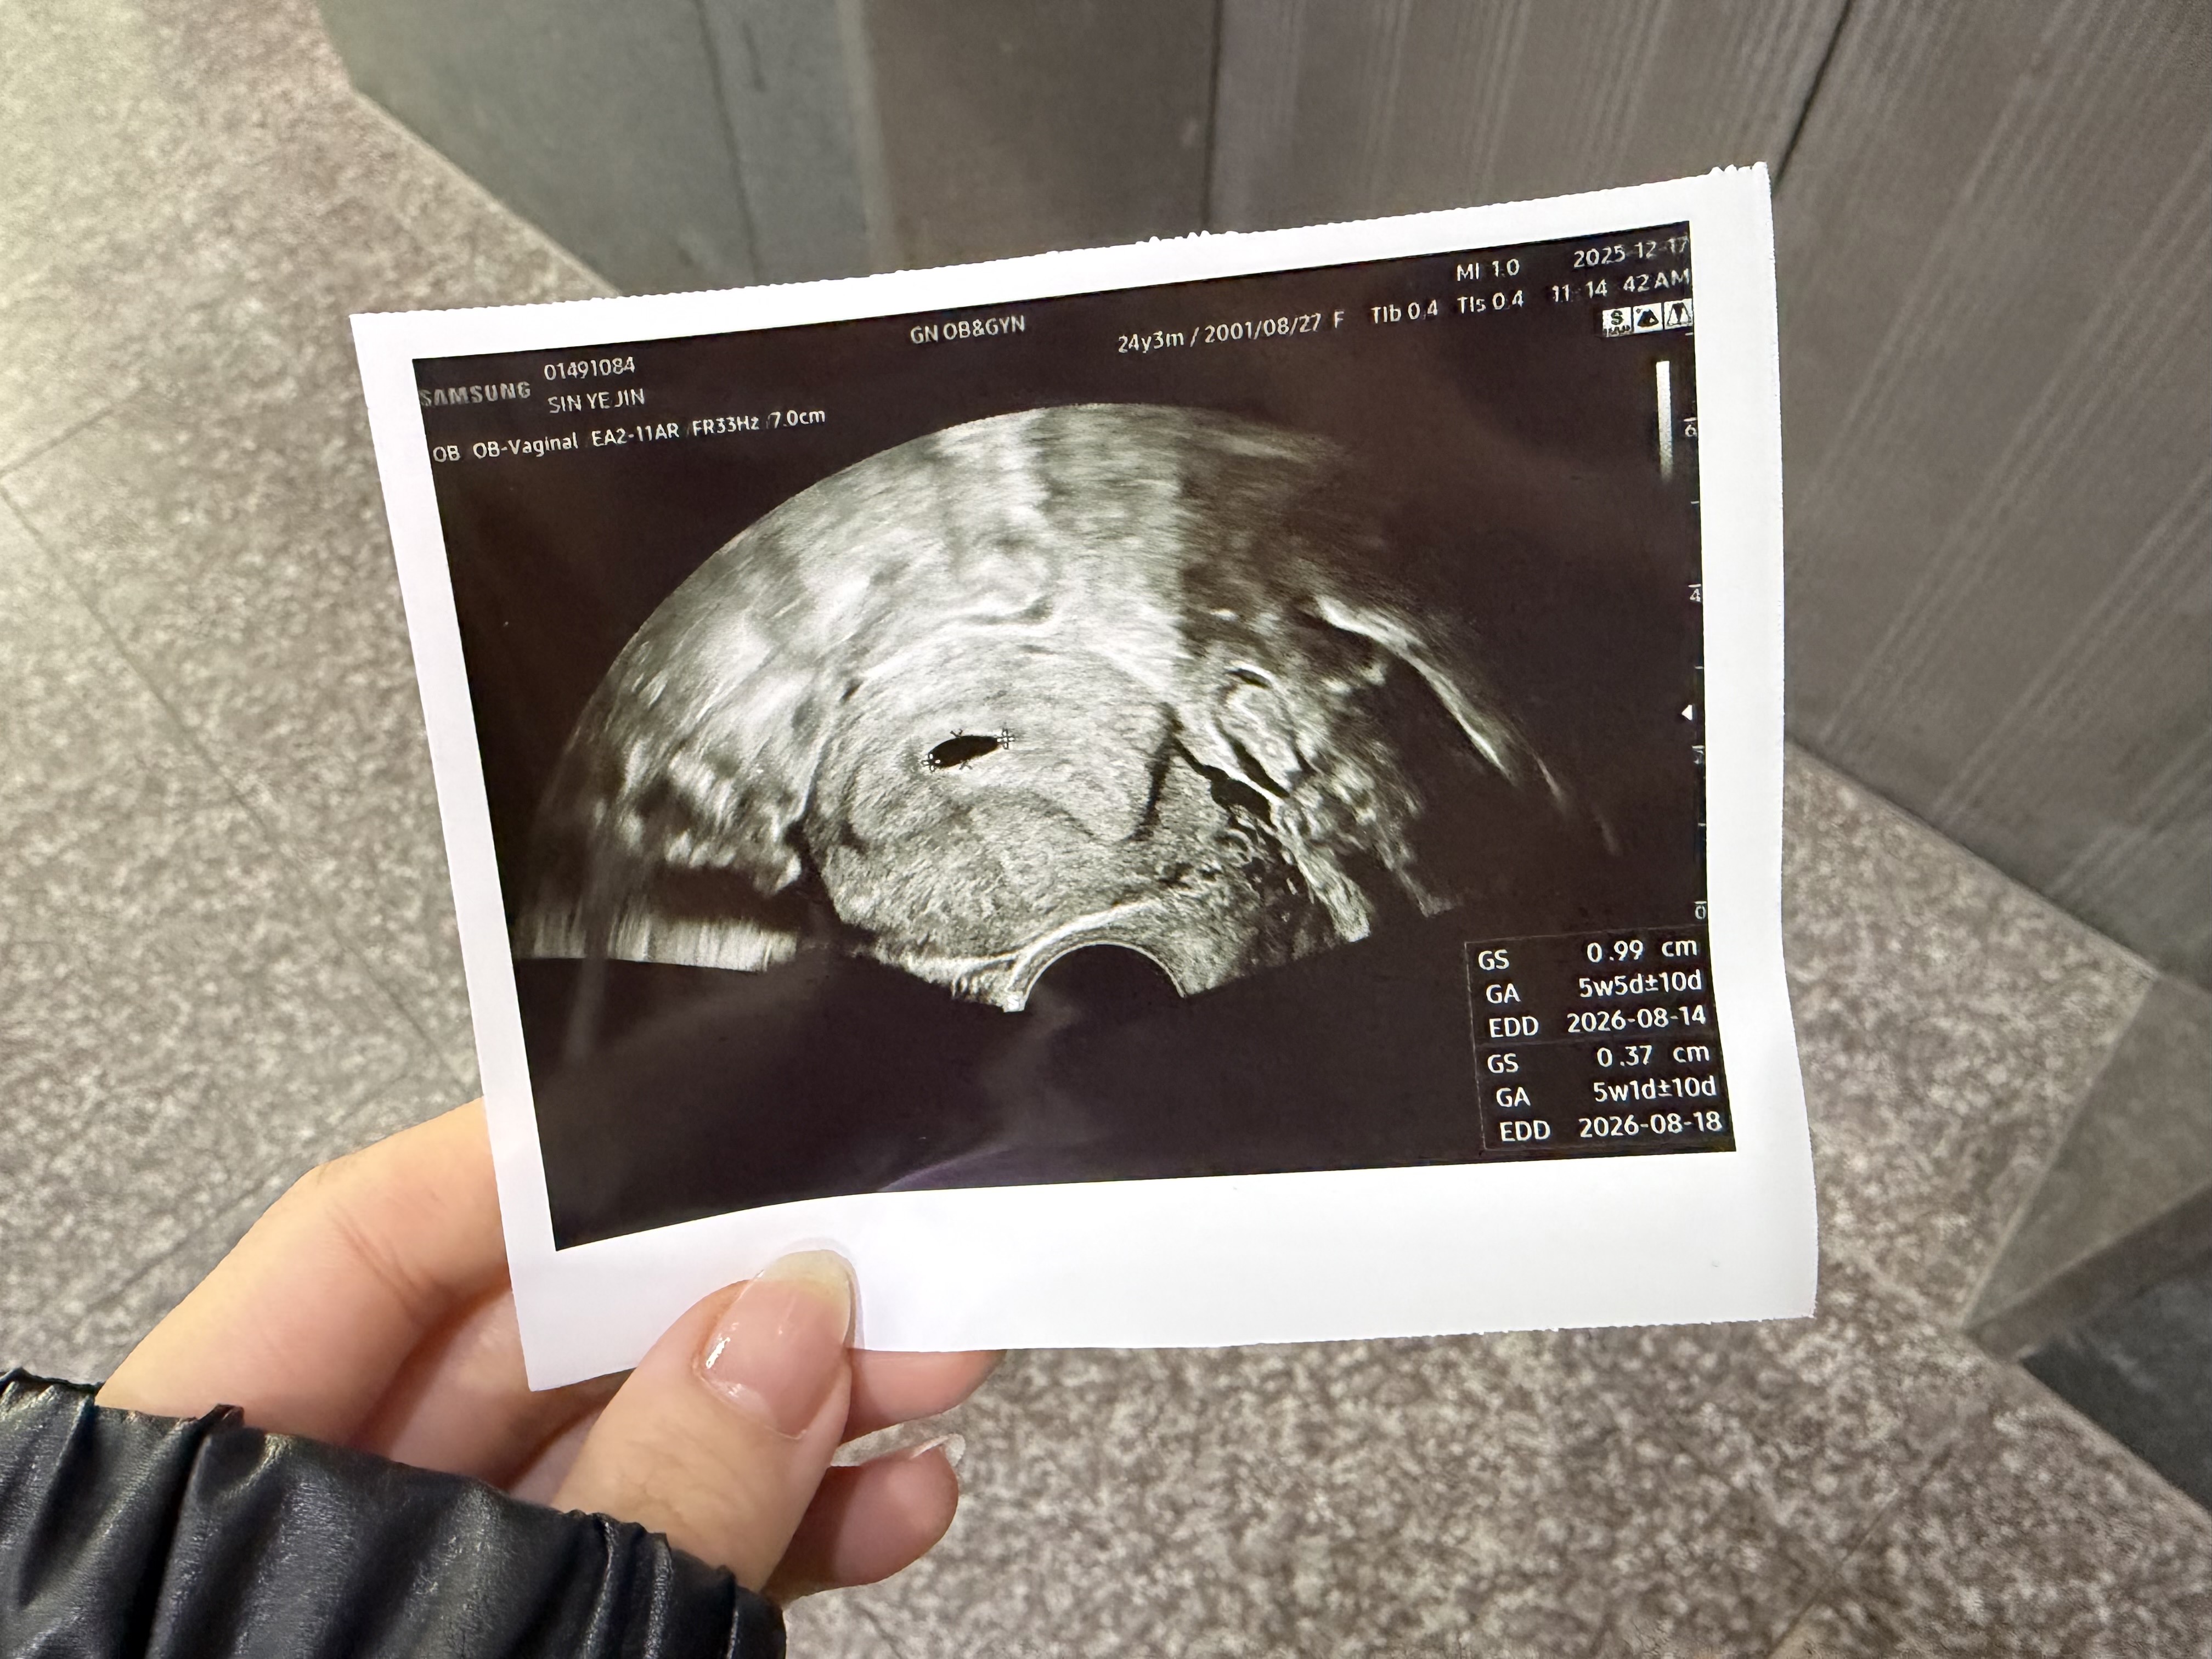

5주차 초음파

5주차 초음파 보고 왔는데 난황이 아직 안보이는게 정상일까용?ㅠㅠ

저랑 같은 상황이시네요ㅎㅎ 저도 12/10 5주2일차에 아기집크기 9mm인데 난황은 못보고 왔어요ㅠㅠ 이번주 주말에 가서 난황+심소 같이 볼 생각으로 기다리고 있어용! 걱정말고 기다려봐요 우리💪🏻🍀

정샹입니당 5주 애기집 6주 난황 7주 심소래요! 자도 아기집만 보고 왔어용